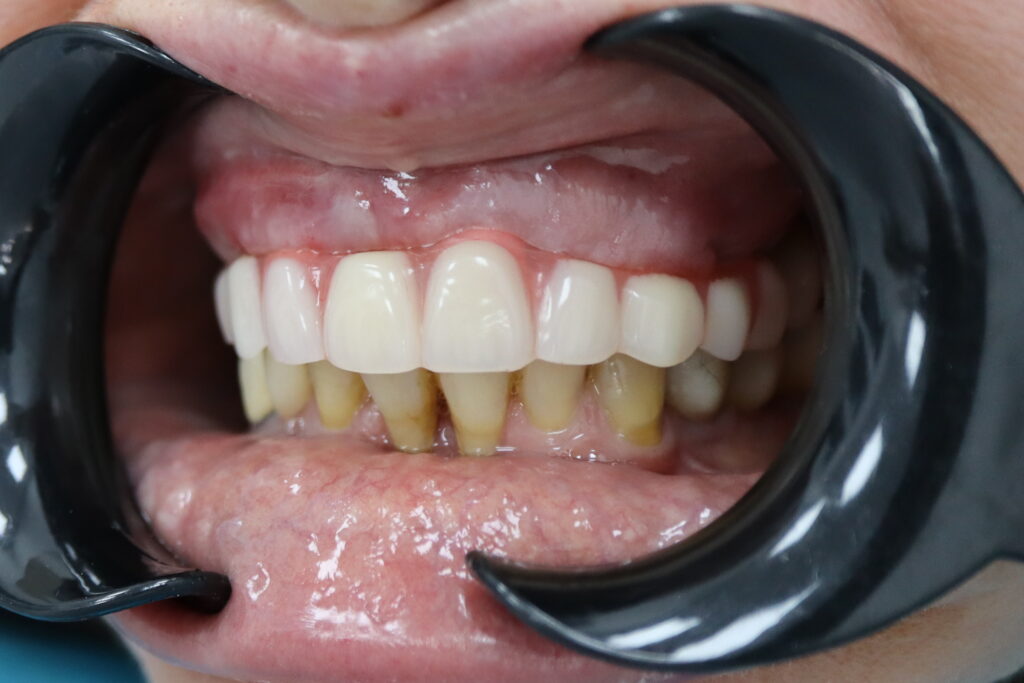

Результаты

Стоимость всего комплекса: 5300 USD (цена указана ориентировочно по курсу НБРБ на день оплаты)

результат имплантации